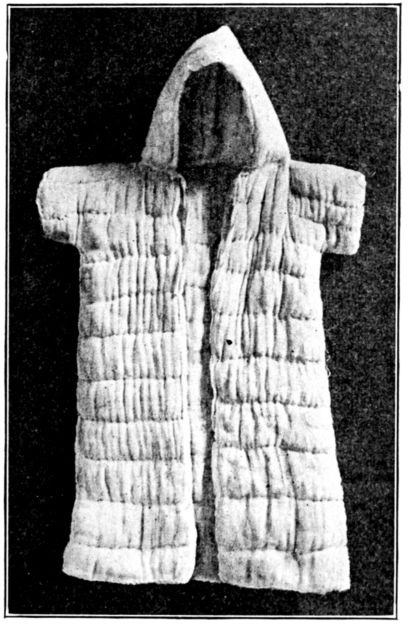

| 171. | Dr. Griffith’s table of fat percentages | 500 |

| 172. | Reverse side of above card | 501 |